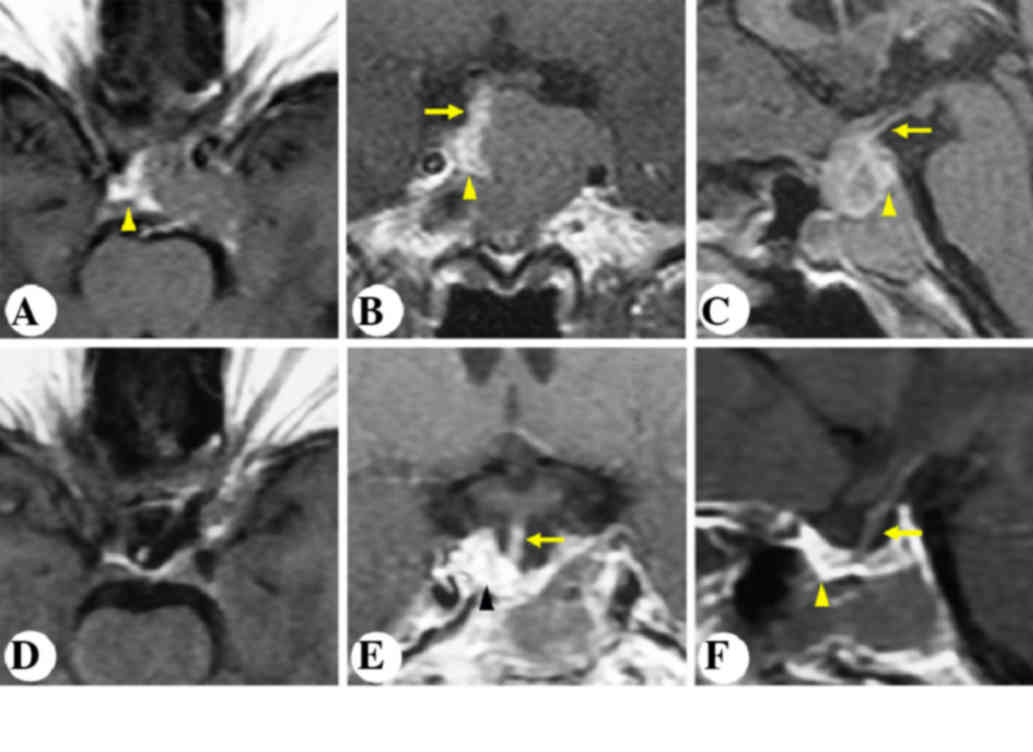

Case 3

A 20-year-old male presented with severe intermittent headache and progressive vision impairment in the right eye for two years. Preoperative MRI is presented in Fig. 4A-C. MRI revealed an intrasellar and suprasellar non-enhancing lesion, invading the left cavernous sinus. The patient underwent unilateral subfrontal surgery. As shown in Fig. 2B, the pituitary stalk was visualized between the optic nerves, and the gland extended distally into the sella turcica. Postoperative MRI revealed gross-total resection of the tumor and an anatomically intact gland and stalk (Fig. 4D-F).

Figure 4.

Patient 3. Representative post contrast T1-weighted images. Preoperative (A) horizontal, (B) coronal and (C) sagittal and postoperative (D) horizontal, (E) coronal and (F) sagittal magnetic resonance imaging of the sellar region. Arrows indicate the pituitary stalk. Arrowheads indicate the pituitary gland.